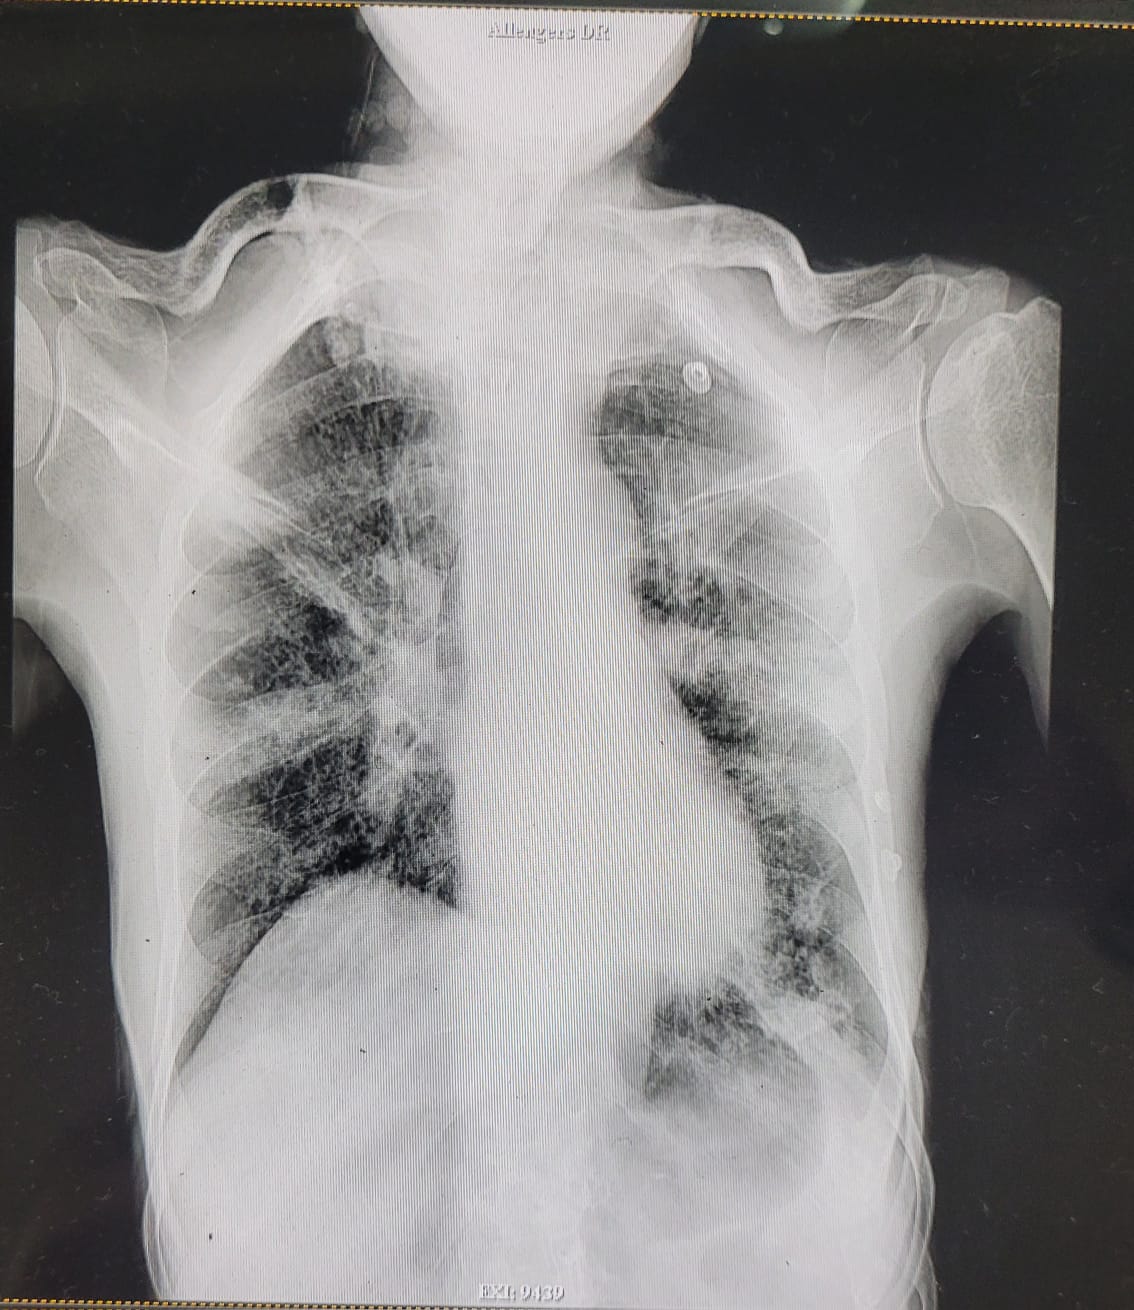

| 321 | IGGMC, Nagpur, Nagpur | P2 | 29-4151 | Ishrath Bano | Consent taken on Paper | 46 Yrs. |

Provisional Diag : Post TB Sequelae

Final Diag : Post TB sequalae with old treated Pyo-pneumothorax with old treated IHD with Seizure |

Post TB Sequelae | Abnormality visible on x-ray |